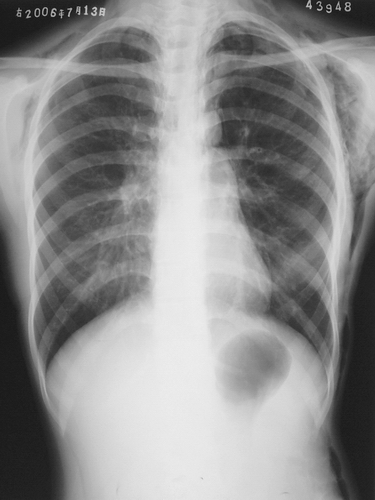

患者,女,18岁。气喘气促多年,加剧半天。摄片如下:

左侧胸壁、腋窝、颈部及右侧颈部皮下软组织内示斑片状、条状低密度气体影,四天后复查片明显吸收好转。